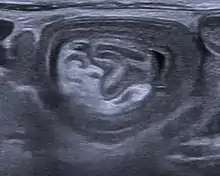

An ultrasound shows a target sign—characteristic for intussusception

An intussusception is often suspected based on history and physical exam, including observation of Dance's sign. A digital rectal examination is particularly helpful in children, as part of the intussusceptum may be felt by the finger. A definite diagnosis often requires confirmation by diagnostic imaging modalities. Ultrasound is the imaging modality of choice for diagnosis and exclusion of intussusception, due to its high accuracy and lack of radiation. The appearance of target sign (also called "doughnut sign" on a sonograph, usually around 3 cm in diameter, confirms the diagnosis. The image seen on transverse sonography or computed tomography is that of a doughnut shape, created by the hyperechoic central core of bowel and mesentery surrounded by the hypoechoic outer edematous bowel.[11] In longitudinal imaging, intussusception resembles a sandwich.[11] It is also called "pseudokidney" sign because hyperechoic tubular centre is covered by a hypoechoic rim producing a kidney-like appearance.[12]